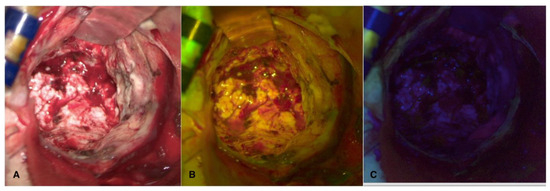

Intraoperative sample visualization allows us to observe the overlap between the two fluorescences within the tumor nodule (Figure 4).

Figure 4. Visualization in white light (A), FL 560 (B), and FL 400 (C) of tumor sample after en-bloc removal.